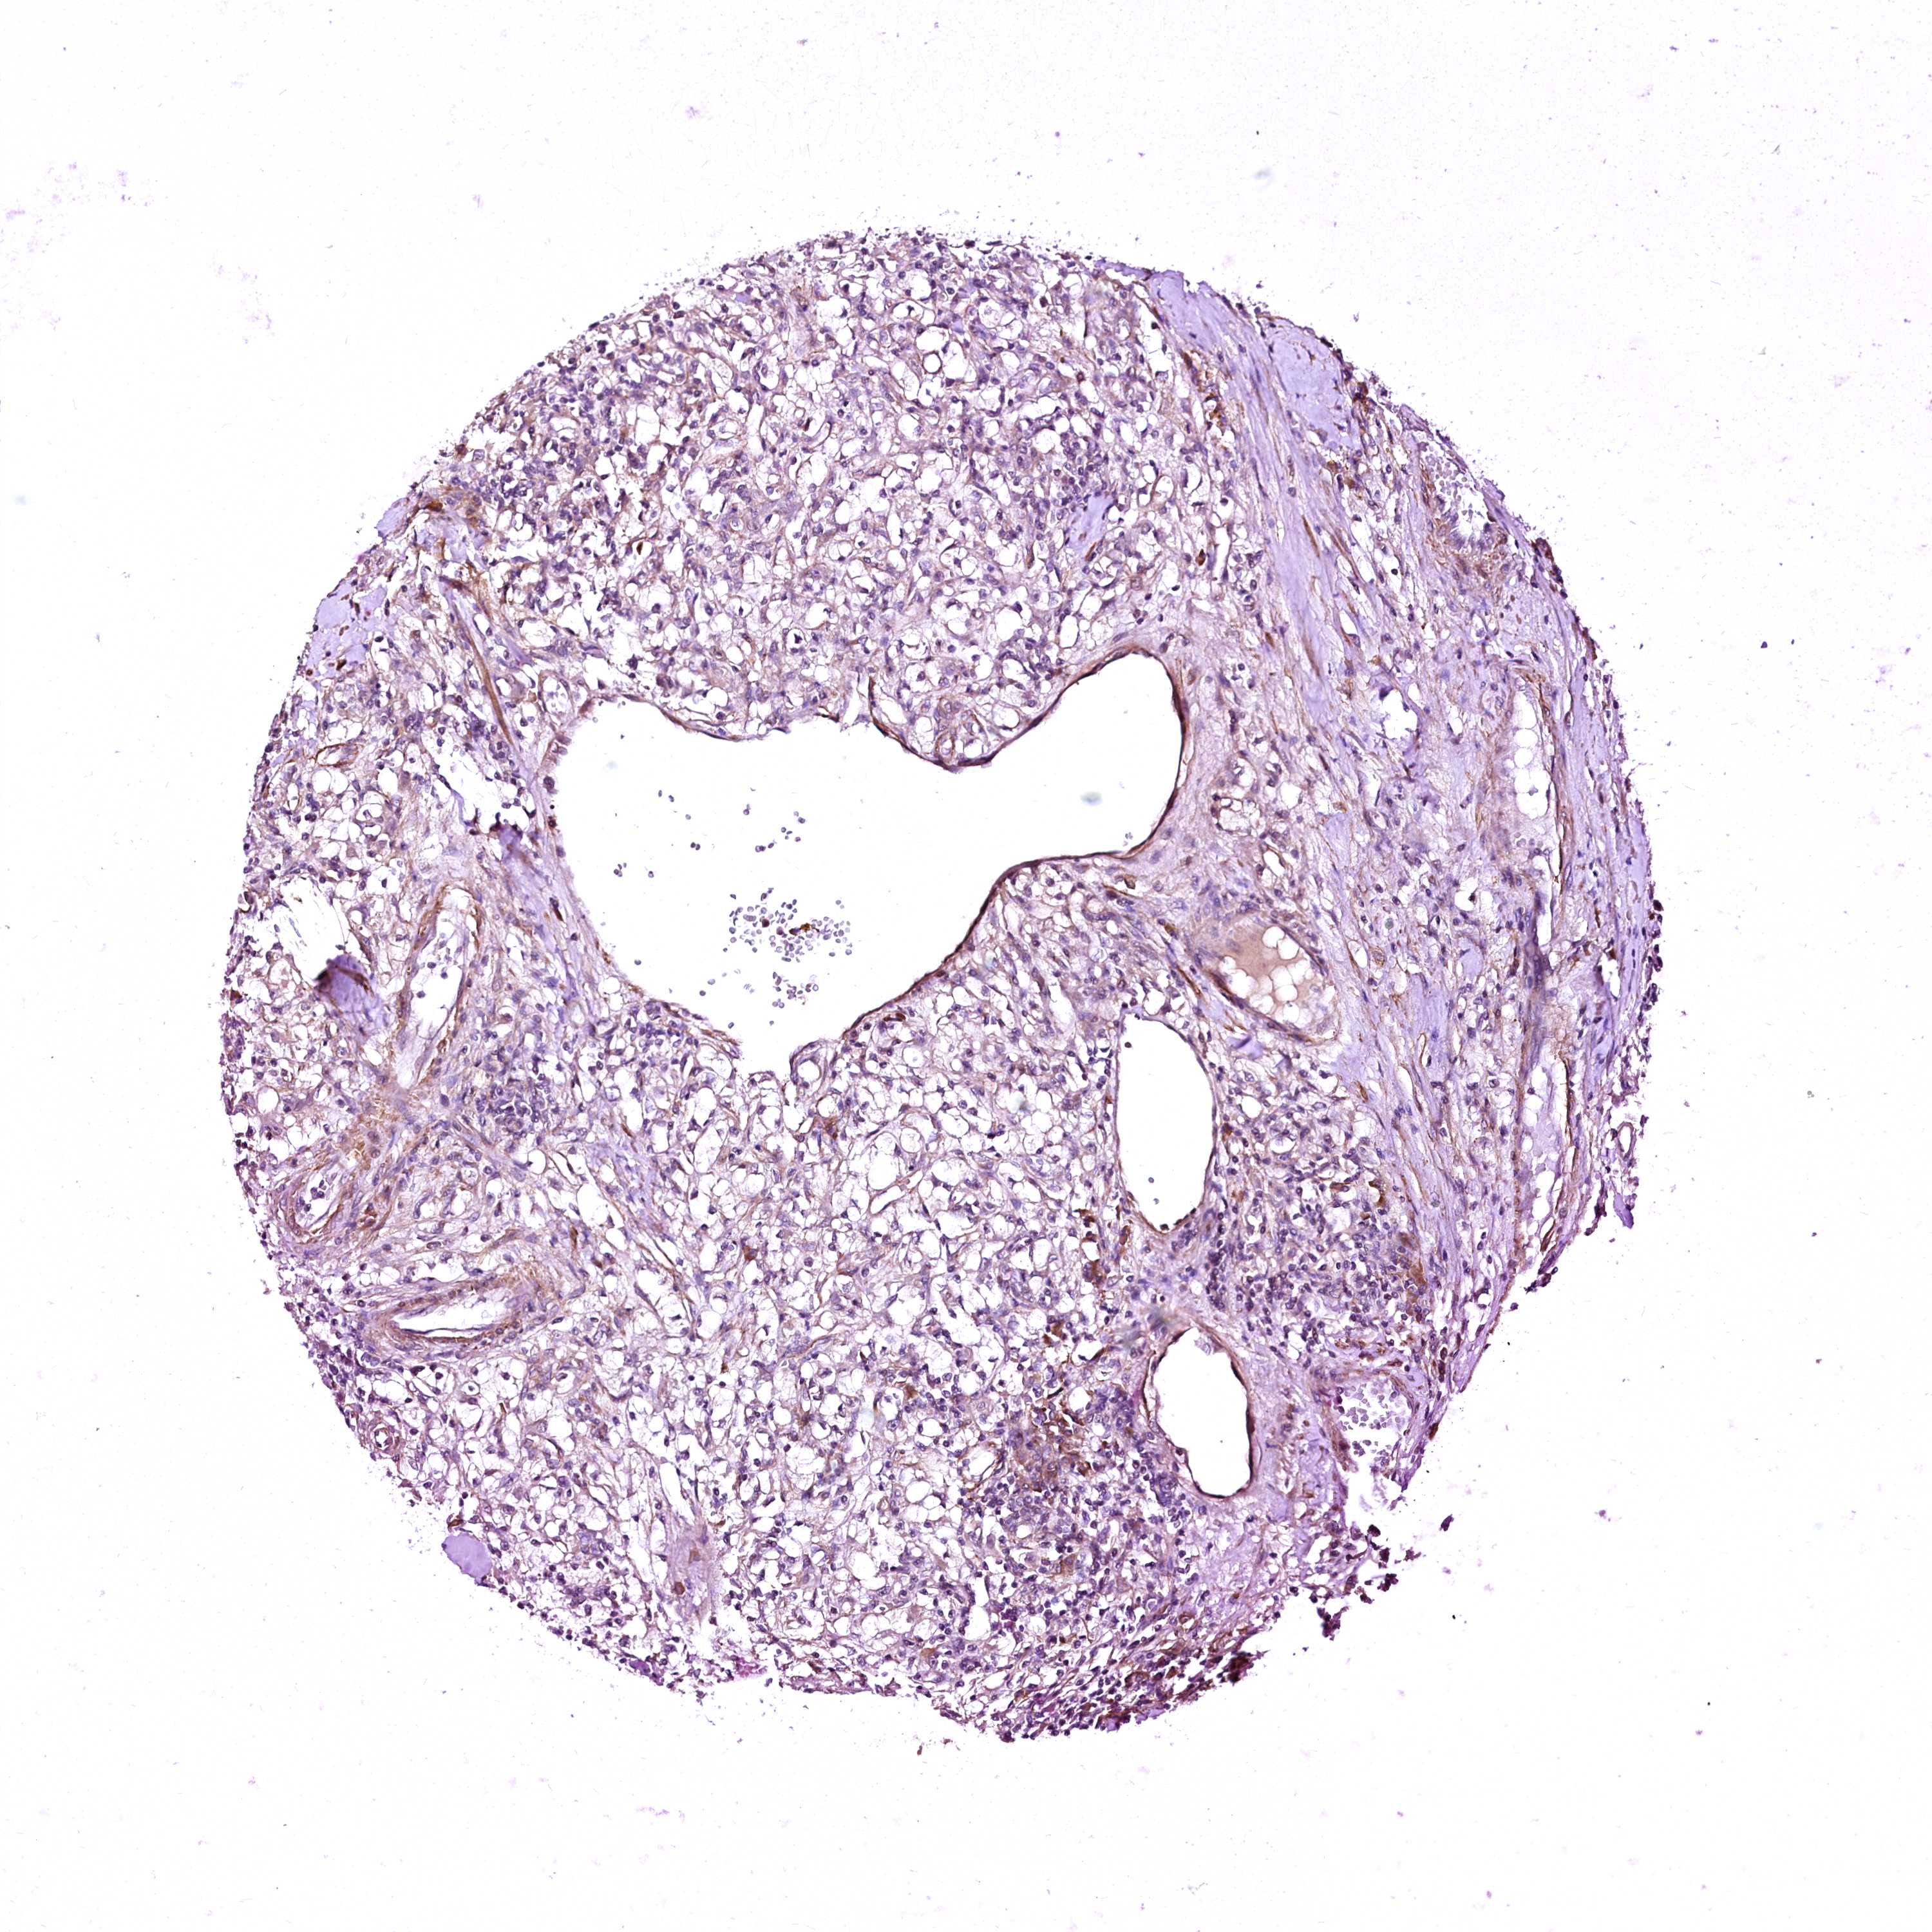

KIDNEY RENAL CLEAR CELL CARCINOMA (VALIDATION) - Interactive survival scatter ploti

GPR176 is not prognostic in Kidney Renal Clear Cell Carcinoma (validation)

: 10.82

Average pTPM 10.0

Number of samples 100